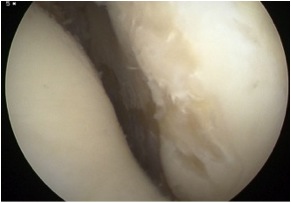

Arthroscopy

Chondral damage capitellum Chondral damage radial head Chondral damage ulnohumeral joint